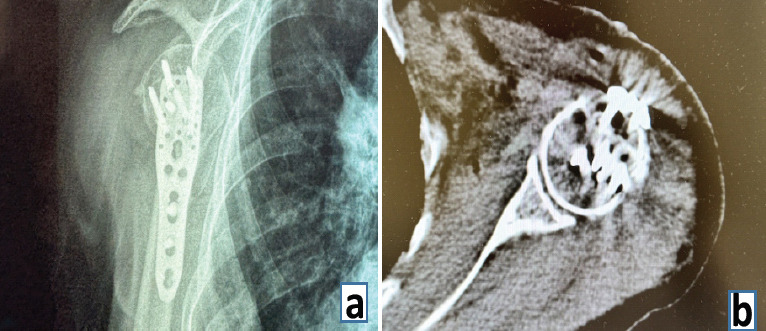

Case report: An 83-year-old Chinese female presented with left shoulder pain and restricted mobility after a ground-level fall. Physical examination revealed a squared shoulder deformity, deltoid muscle strength of 2/5, and sensory abnormalities in the axillary nerve territory. Radiographs confirmed anteroinferior humeral dislocation with comminuted greater tuberosity fracture. Closed reduction attempts failed twice. Three-dimensional.

Ct demonstrated: ① Hill-Sachs defect engaging the anterior glenoid rim; ② coronally split greater tuberosity fragment interposed in joint space; ③ 25 mm medial displacement of proximal humerus. The deltopectoral approach exposed the long head of biceps tendon traversing humeral head, forming complex interposition. Kirschner wire (K-wire) joystick technique was employed to disimpact osseous blocks. Tension band suturing combined with locking plate fixation was performed. Biceps tendon integrity was completely preserved. The post-operative course was uneventful, with satisfactory functional and radiographic outcomes and no recurrent dislocation during follow-up.